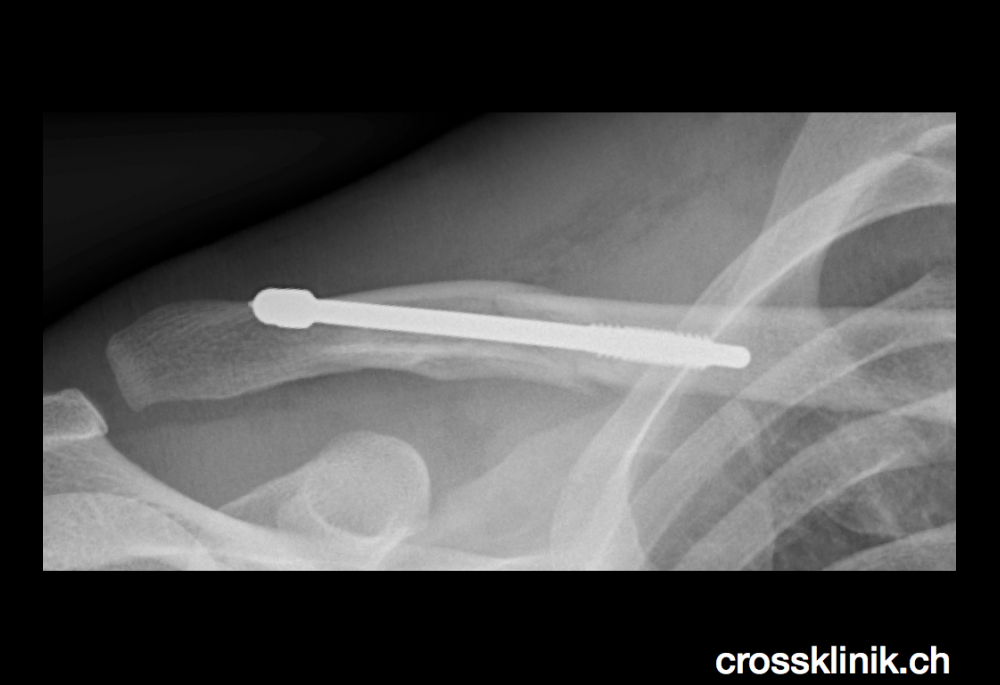

And by they way, Cancellara — here’s what his collarbone looked like just this past March:

Like many things, it was nothing a little screw wouldn’t fix: